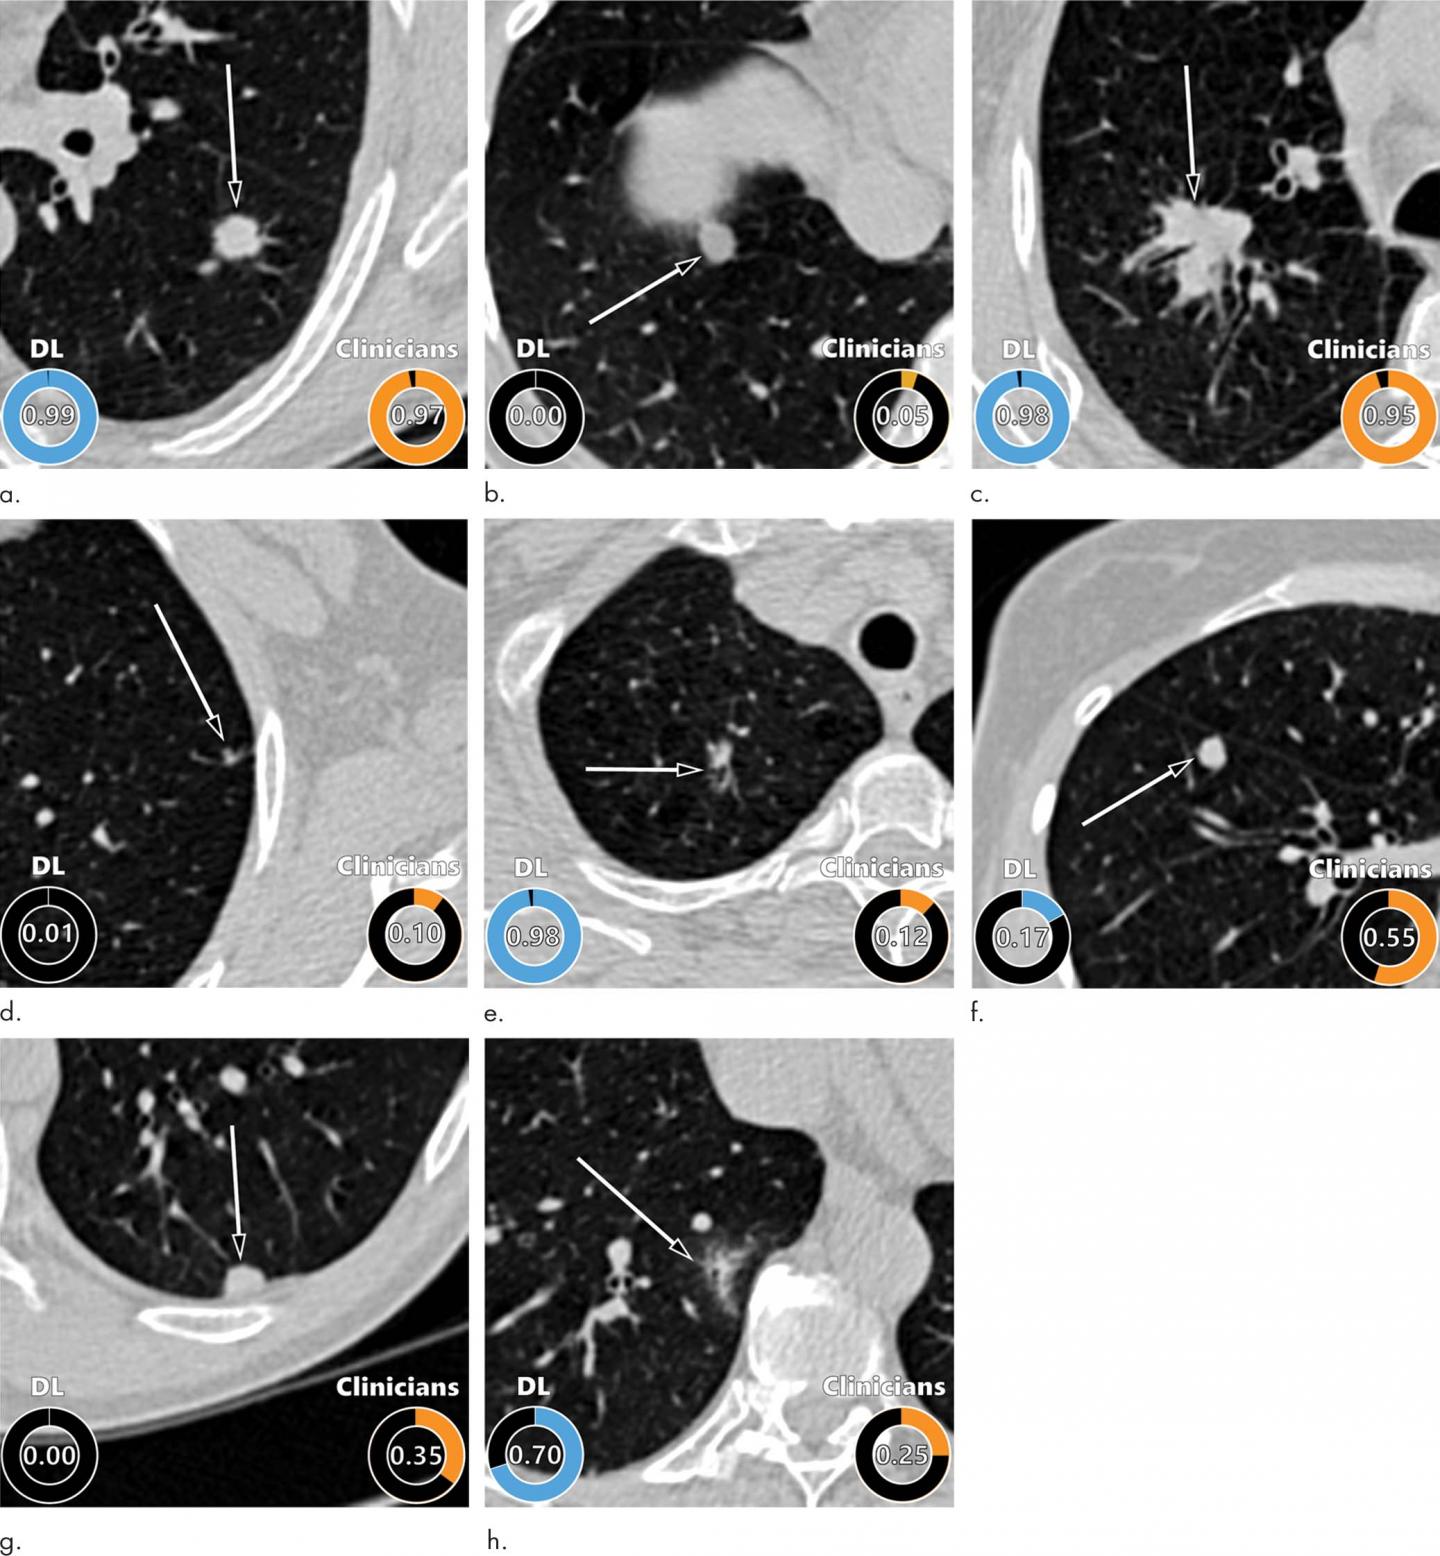

For the new study, researchers developed an algorithm for lung nodule assessment using deep learning, an AI application capable of finding certain patterns in imaging data. The researchers trained the algorithm on CT images of more than 16,000 nodules, including 1,249 malignancies, from the National Lung Screening Trial. They validated the algorithm on three large sets of imaging data of nodules from the Danish Lung Cancer Screening Trial.

The deep learning algorithm delivered excellent results, outperforming the established Pan-Canadian Early Detection of Lung Cancer model for lung nodule malignancy risk estimation. It performed comparably to 11 clinicians, including four thoracic radiologists, five radiology residents and two pulmonologists.